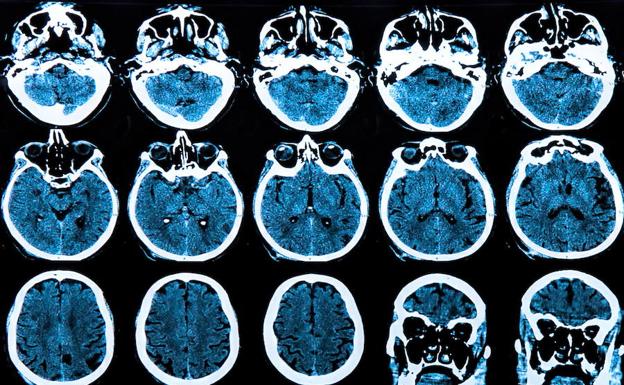

Investigadores de la Universidad de Cambridge y de Lund han descubierto una nueva forma de enfrentarse a las partículas tóxicas que destruyen las células cerebrales sanas